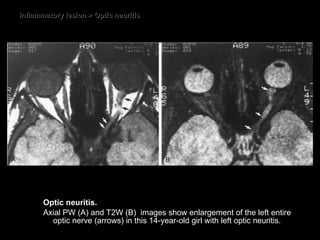

Optic neuritis CT some enlargement of the optic nerve some degree of contrast enhancement.  MRI Thickened and hyperintense T2WI. Diffuse enhancement within the nerve on T1WI FS. Evidence of MS plaques

Inflammatory lesion > Optic neuritis Optic neuritis.  Axial PW (A) and T2W (B)  images show enlargement of the left entire optic nerve (arrows) in this 14-year-old girl with left optic neuritis.